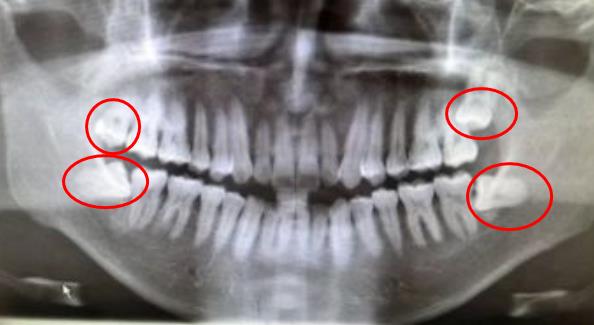

盡頭牙拔除之前就是為(wei) 了拍片看清楚智齒是什麽(me) 樣子的,以方便醫生製定拔牙方案,給出合適的拔牙價(jia) 格。至於(yu) 是拍全景片還是要拍CT片,這就要看情況了,有的可能先拍全景片後,情況不是很明確還要繼續拍CT片呢。目前拍全景片價(jia) 格一兩(liang) 百,CT片三四百左右。

全景片中可以看出有兩(liang) 顆上頜智齒有兩(liang) 顆下頜智齒